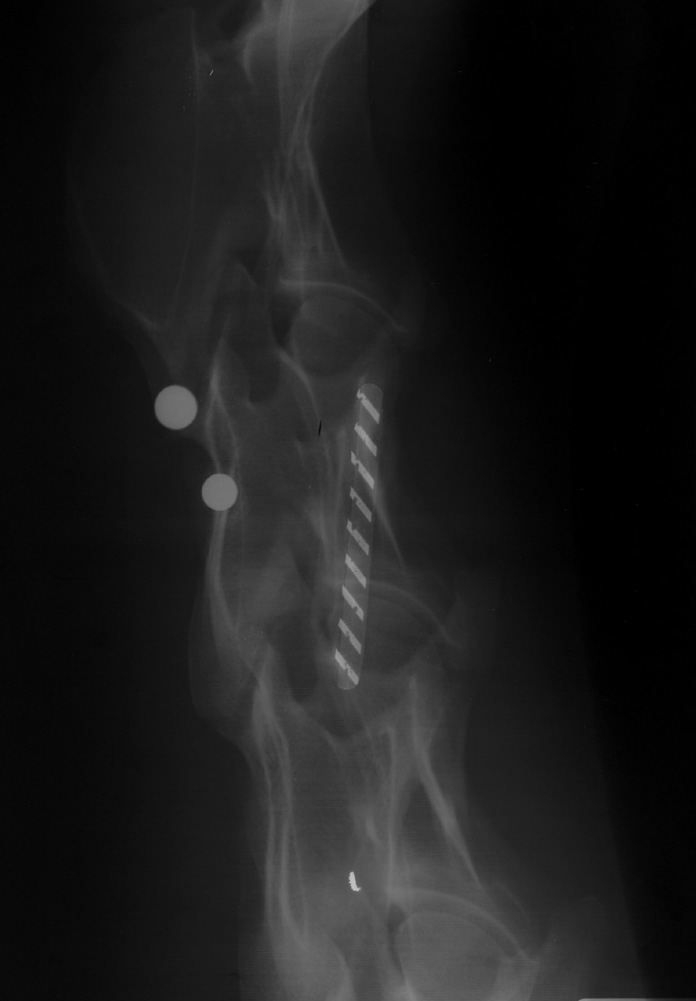

Hair in Cassette |

White artifacts due to horse hair within the cassette during exposure of the film. Plastic closer inside cassette (striped object), round balls are put on the horse neck for measurement purposes. They are on the outside of the horse. One is larger than the other. Which one?